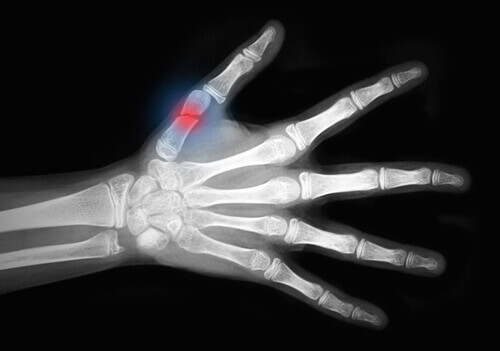

Bu hastalık, kemiklerinizi zayıflatır ve kırılgan hale getirir. Bileğiniz, kalçanız ya da omurga sütununuz, kırılma riski en yüksek olan alanlardır.